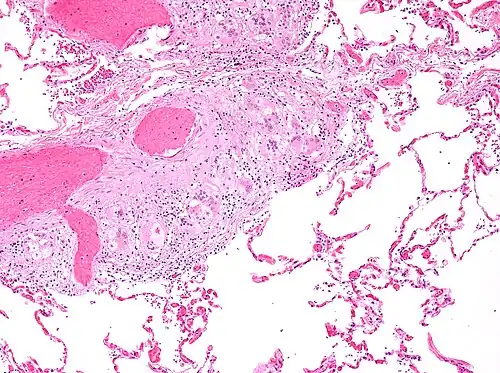

Sarcoidosis is characterized by the formation of non-necrotizing ("non-caseating") granulomas in various organs and tissues.[95] Giant cells, specifically Langhans giant cells, are often seen in sarcoidosis.[96] Schaumann bodies seen in sarcoidosis are calcium and protein inclusions inside of giant cells as part of a granuloma.[97] Asteroid bodies can be seen in sarcoidosis.[97] Hamazaki–Wesenberg bodies can be seen in lymph nodes and more rarely in lung biopsies with sarcoidosis and are inclusion bodies of lysosomes with protein, glycoprotein and iron.[98]

Sarcoidosis in a lymph node

Pulmonary sarcoidosis with granulomas with Langhans giant cells and asteroid bodies